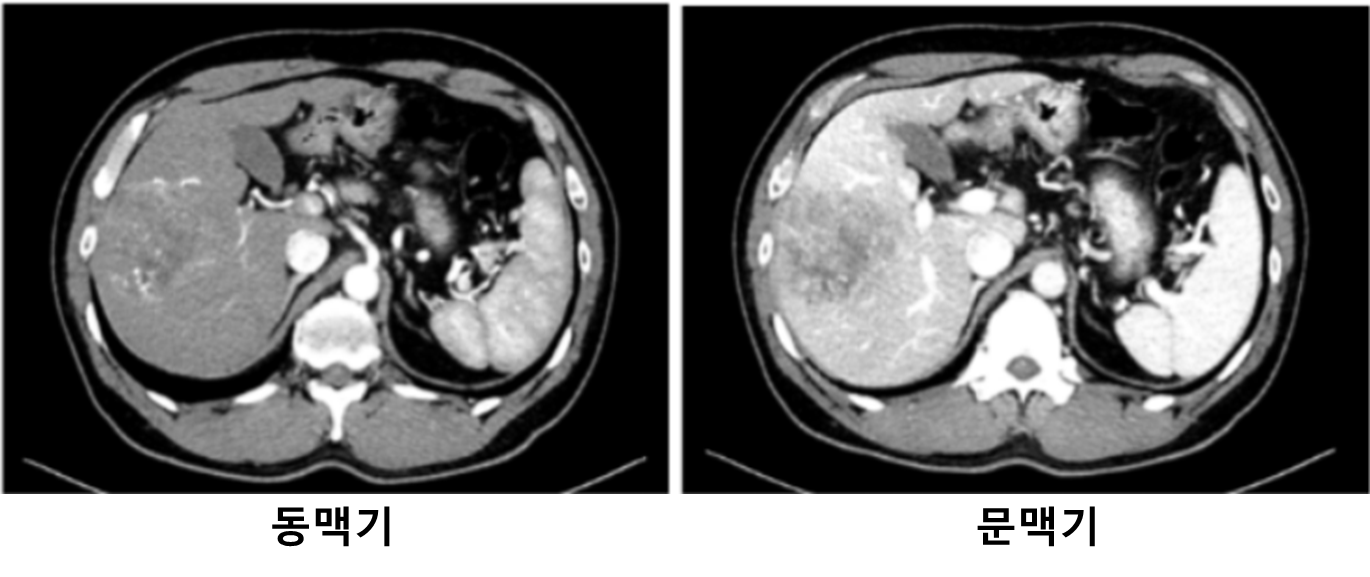

51세 남자가 1개월 전부터 오른쪽 윗배가 불편하다며 병원에 왔다. 군대 신검에서 B형간염이라는 말을 들었으나 정기적인 검사는 받지 않았다고 한다. 혈압 140/90 mmHg, 맥박 78회/분, 호흡 19회/분, 체온 36.5 ℃이다. 오른쪽 윗배를 눌렀을 때 약간의 불편감을 호소한다. 복부 컴퓨터단층촬영사진이다. 혈액검사 결과는 다음과 같다. 진단은?

CT: Single mass at Rt. hepatic lobe, early enhancemnet-early washout

만성 B형 간염 환자의 dynamic CT상 1cm 이상의 mass에서 early enhancement-early washout 소견이 관찰되므로 간세포암(HCC)으로 진단한다.

• Dynamic CT상 간 우엽large mass가 관찰되며, 동맥기에 주변 간조직보다 조영증강되고 문맥기에는 주변 간조직보다 조영되지 않는 early enhancement-early washout 소견이 관찰된다.

• CHB 환자의 dynamic CT상 1cm 이상 mass가 관찰되며, early enhancement-early washout 소견이 확인될 경우 biopsy없이 간세포암(hepatocellular carcinoma,HCC)로 진단가능하다.